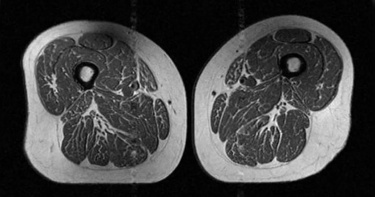

不少人平時愛吃零食、碳酸飲料、即食食品等超加工食品(UPF)。不過,醫師蔡明劼指出,最新研究發現,長期攝取超加工食品,可能讓大腿肌肉出現類似「A5和牛」油花的脂肪堆積,影響肌肉功能,導致肌力衰退、走路速度變慢,甚至進一步損害關節健康。內分泌專科醫師蔡明劼在臉書發文,分享一篇2026年刊登在《放射學》(Radiology)期刊的最新研究,分析了615名、年約60歲、具有退化性膝關節炎風險的受試者,研究結果發現,攝取越多超加工食品的人,大腿肌肉裡的脂肪浸潤就越嚴重。最新研究顯示,攝取超加工食品越多,大腿肌肉脂肪浸潤就越明顯。(圖/翻攝自臉書/蔡明劼醫師 健康。瘦身)蔡明劼PO出研究中的核磁共振影像,照片中比較2名BMI相近的女性,左圖的女性,攝取超加工食品佔一天總熱量的29.5%;右圖的女性則攝取87.1%,「儘管兩者的BMI相近,腰圍以及大腿油花指數竟然有天壤之別」。蔡明劼表示,這種現象在男女身上都一樣明顯,代表攝取超加工食品會導致肌肉品質下降。蔡明劼說明,大腿肌肉功能對於膝關節的穩定性至關重要,一旦肌肉品質被脂肪取代,支撐力就會下降,導致肌力衰退、走路速度變慢,進而影響整體的活動能力,還可能引發發炎反應及功能性影響,進一步損害關節健康。另外,研究也發現,考量到反映內臟脂肪分布的中央型肥胖,腰圍與大腿肌肉脂肪的關聯性比看BMI更明顯。至於什麼是超加工食品(UPF)?蔡明劼解釋,超加工食品通常是經工業化生產方法製造,並加入大量香料、著色劑、乳化劑等化學添加物,以增強保存期限與口感吸引力的食品 。例如,碳酸飲料、包裝零食、即食餐點等,這類食物多半高鹽、高糖、高脂肪,但卻缺乏纖維、蛋白質與微量元素等必要營養。蔡明劼提醒「即使你的體重(BMI)看起來還算正常,不健康的飲食依然會從內部侵蝕你的肌肉品質」,若想保住結實的大腿,建議減少攝取超加工食品比例、增加天然全食攝取並適度身體活動,給予肌肉正確的營養支持,並鍛鍊肌肉健康與功能,避免因疼痛或久坐導致的肌肉萎縮,「別讓你的大腿真的變成A5和牛,畢竟你的肌肉是用來走路的,不是用來品嚐的」。